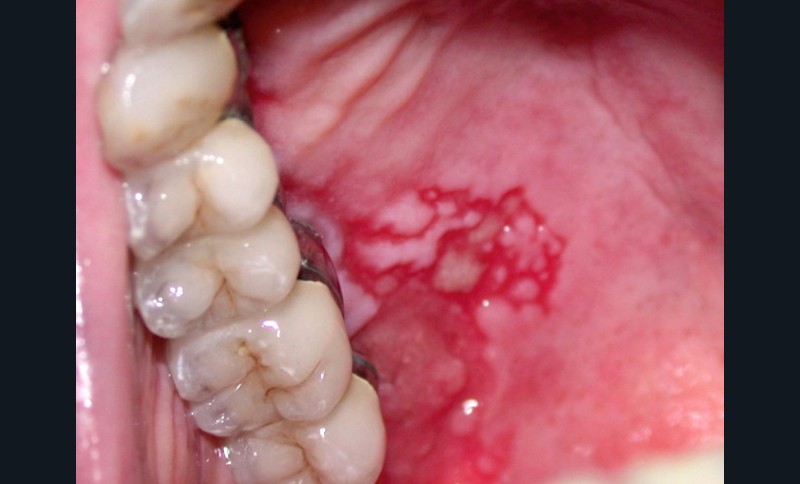

Érythroplasie associée à un lichen oral : elle se caractérise par des lésions kératinisées plus ou moins réticulées ou sous forme de plages et plaques associées à une macule, plage, plaque érythémateuse bien limitée (fig. 3).